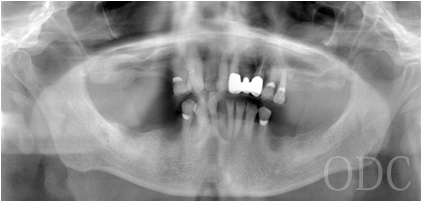

術 前

術前

初診時87歳、男性。上顎は歯周病により残存歯を長期的に機能させることが困難と判断し、全て抜歯。出来る限り早期の咬合機能の回復と審美性の実現が求められ、上顎は「4本のインプラントで失った全ての歯を固定し、手術当日から噛む機能を回復させることが可能」なオールオン4という術式を選択。オールオン4は「治療期間」「経済性」「審美性」「外科的侵襲」などのあらゆる負担を軽減した全く新しいコンセプトの画期的なインプラント治療です。 下顎の欠損部位に対しても、術前の診査診断をしっかり行い合計5本のインプラントを埋入しました。

パノラマX線写真

術 後

術前・術後のパノラマX線写真です。上顎(オールオン4)は4本のインプラントにチタンフレームの上部構造が固定されているのがおわかりになると思います。下顎のインプラント埋入部位、上顎のインプラントの本数、再度写真をご覧いただくと、とてもインプラントが埋入されているとわからない程の外観、下顎の残存歯(元々の自分の歯)とも区別がつかない審美性が実現されています。